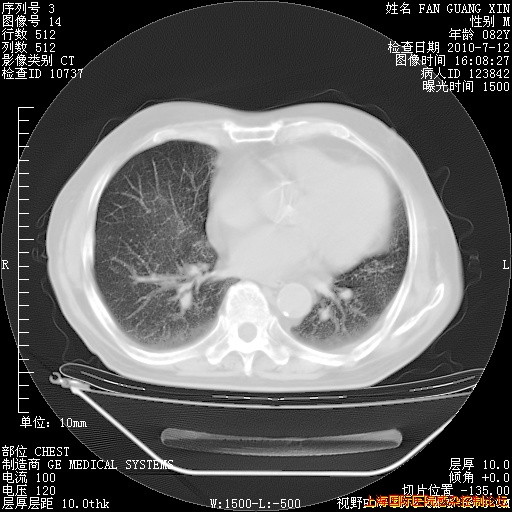

今天复查CT

今天CT

整整相隔30天的肺部CT好像有所好转啊。甲强龙减量第3天,需要观察体温。